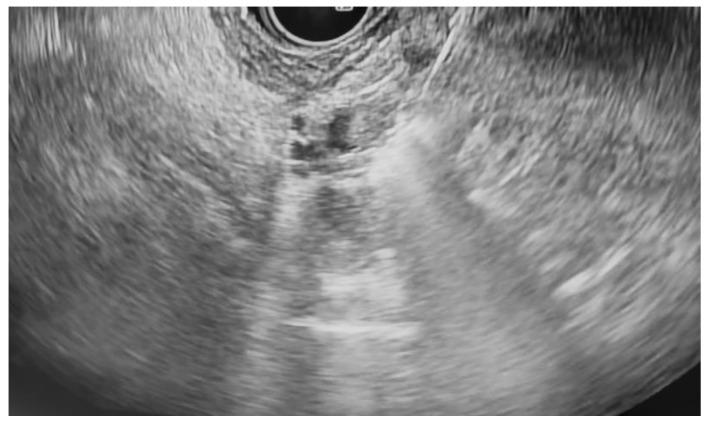

Pancreatic neoplasms, including adenocarcinoma, pancreatic neuroendocrine tumors (pNETs), intraductal papillary mucinous neoplasms (IPMNs), and high-grade cystic lesions, often require surgical resection as a form of curative treatment. However, comorbidities and high-risk features may preclude surgery. Endoscopic ultrasound-guided radiofrequency ablation (EUS-RFA) has emerged as a minimally invasive alternative with proven cytoreductive efficacy in solid tumors. This case series evaluates the safety and efficacy of EUS-RFA in patients with various unresectable, non-metastatic pancreatic neoplasms. A retrospective review was conducted on eight patients who underwent EUS-RFA at our institutions between July 2021 and February 2025. All patients were deemed unsuitable surgical candidates due to comorbidities such as advanced age, cardiovascular disease, renal insufficiency, and COPD or due to patient resistance to surgical intervention. EUS-RFA was performed using a 19-gauge RFA needle (Taewoong Corporation). Follow-up imaging was conducted 3 to 6 months after the completion of RFA treatment. All eight patients demonstrated a good to excellent response in terms of tumor size reduction. The most notable response was observed in a patient with pNET, resulting in complete resolution from 15.6 × 12.0 mm to 0.0 × 0.0 mm after two RFA treatments. Other neoplasms, including pancreatic adenocarcinoma and intraductal papillary mucinous neoplasms (IPMNs), also demonstrated significant reductions. Mild post-procedure complications, including pancreatitis and abdominal pain, were noted in three cases. EUS-RFA is a promising alternative for managing unresectable pancreatic neoplasms in high-risk patients. Our findings support its use across various tumor types with favorable outcomes and minimal complications, reinforcing its role in expanding therapeutic options beyond surgery.

胰腺肿瘤,包括腺癌、胰腺神经内分泌肿瘤(pNETs)、导管内乳头状黏液性肿瘤(IPMNs)和高级别囊性病变,通常需要手术切除作为一种根治性治疗方式。然而,合并症和高风险特征可能使手术无法进行。内镜超声引导下射频消融术(EUS-RFA)已成为一种微创替代方法,在实体肿瘤中具有已被证实的减瘤疗效。本病例系列评估了EUS-RFA在各种无法切除的非转移性胰腺肿瘤患者中的安全性和有效性。对2021年7月至2025年2月期间在我们机构接受EUS-RFA治疗的8例患者进行了回顾性研究。所有患者均因高龄、心血管疾病、肾功能不全和慢性阻塞性肺疾病等合并症或患者对手术干预的抗拒而被认为不适合手术。使用19号射频消融针(太永公司)进行EUS-RFA。在射频消融治疗完成后3至6个月进行随访成像。所有8例患者在肿瘤缩小方面均表现出良好至优异的反应。在1例pNET患者中观察到最显著的反应,经过两次射频消融治疗后,肿瘤从15.6×12.0毫米完全消退至0.0×0.0毫米。其他肿瘤,包括胰腺腺癌和导管内乳头状黏液性肿瘤(IPMNs),也表现出显著缩小。3例患者出现了轻度术后并发症,包括胰腺炎和腹痛。EUS-RFA是管理高危患者无法切除的胰腺肿瘤的一种有前景的替代方法。我们的研究结果支持其在各种肿瘤类型中的应用,具有良好的疗效和最小的并发症,强化了其在扩展手术以外治疗选择方面的作用。